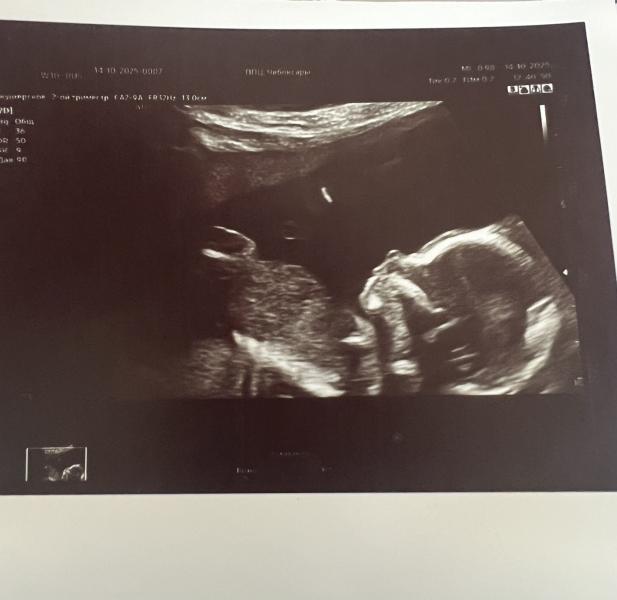

На узи все хорошо , никаких признаков ХА не увидели.

😍😍😍это что за сладость там на экране ,тоже ходила к генетику ,и она мне сказала ,что риски низкие ,переживать вообще не о чем )))узи все отличные ,я успокоилась и пошла жить свои прекрасные моменты беременности ❤️все будет хорошо 🌹